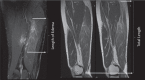

The aim of this work was to study semimembranosus musculotendinous injuries (SMMTI) and return to play (RTP). The hypothesis is that some related anatomic variables of the SM could contribute to the prognosis of RTP. The retrospective study was done with 19 athletes who suffered SMMTI from 2010 to 2013 and in whose cases a 3.0T MRI was performed. We evaluated the A, B, C SM regions damaged and calculated the relative length and percentage of cross-sectional area (CSA) affected. We found the correlation of these variables with RTP. The data was regrouped in those cases where the part C of the injury was of interest and those in which the C region was unscathed (pooled parts). We used the Mann-Whitney U test and there was a higher RTP when the injury involved the C part of SM (49.1 days; 95% CI [27.6– 70.6]) compared to non-C-part involvement (27.8 days; 95% CI [19.5–36.0]). The SMMTI with longer RTP typically involves the C part with or without participation of the B part. In daily practice, the appearance on MRI of an altered proximal tendon of the SM indicates that the injury affects the C region and therefore has a longer RTP.